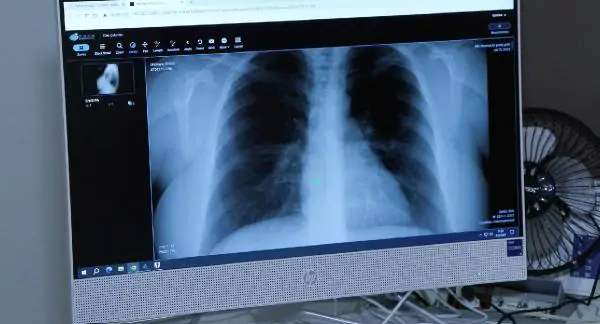

“Afrika sıcaklarıyla akciğer ve alerji hastalıkları da arttı”

Uzmanından ‘Afrika sıcakları akciğer hastalıklarını tetikledi’ açıklaması

Nisanur ŞENTÜRK-Erdi DEMİR/İSTANBUL, (DHA)- Türkiye’de yaşanan Afrika sıcaklarının kişilerde kronik akciğer ve alerjik hastalıkları tetiklediğini belirten Göğüs Hastalıkları Uzmanı, Uzm Dr. Hacer Ofluoğlu, “Geçen yaza oranla acile ve göğüs polikliniklerine başvurular arttı. Sadece görev yaptığım hastanede bile yapılan alerji, solunum fonksiyon testlerinde yüzde 25-30 artış saptadım. Özellikle şu ana kadar hiçbir akciğer ve alerji sorunu olmayan kişilerde yükselen rakamlar tespit ettik. Bu da yüzde 10 arttı” dedi.

Aşırı sıcak hava dalgaları, yoğun nem, birden gelişen ısı değişimi ve rüzgârla bir gelen tozun kronik akciğer ve alerjik hastalıkları tetiklediğini söyleyen Medicana Çamlıca Hastanesi Göğüs Hastalıkları Uzmanı, Uzm Dr. Hacer Ofluoğlu, “Aşırı sıcaklar bu tür hastalıkların ortaya çıkma olasılığını son yıllarda artırmaktadır. Polenlerin çöl tozlarıyla uzun mesafeler sürüklenmesi, aerosollerin alerjik hastalıkları daha uzun süreler karşımıza çıkarması, sadece polen dönemlerinde ya da mevsimsel alerjik dönemlerde değil yılın farklı mevsimlerinde de artık ortaya çıkma ve karşılaşma olasılığımızı artırmaktadır. Sıcaklıkların ve nemin artışı, kronik akciğer hastalıklarında da solunum yollarında mukozanın ısınması ve öksürük semptomlarına yol açıyor” açıklamasında bulundu.

Uzm Dr. Ofluoğlu, “Sağlıklı bir solunum yapabilmemiz için ortamda istenilen nem düzeyi yüzde 30 ila 50’dir.Son yıllarda artan nem düzeyleri ise öksürük, nefes darlığı, hırıltı, alerjik limit belirtilerinde kötüleşme yani özellikle hapşırık ve burun tıkanıklığı vakalarında artışa neden olmuştur. Bunlar mukoza üzerinde ısınma, nemin yapmış olduğu mukozal hasar, mukoza miktarlarının artışı ve mukus kıvamının koyulaşması nedeniyle bu tür belirtileri hastanın akciğerde daha fazla hissetmesine yol açmaktadır. Çöl tozlarıyla sürüklenen polenler, mantar sporları, virüsler, bakteriler uzun süre havada asılı kalabiliyor. Sağlıklı akciğerde dahi solunumsal semptomları artırabiliyor. Bunun yanında özellikle kronik akciğer sorunu olanlarda bu tür semptomların şiddetlenmesine ve acil başvurularının artışına neden oluyor” dedi.